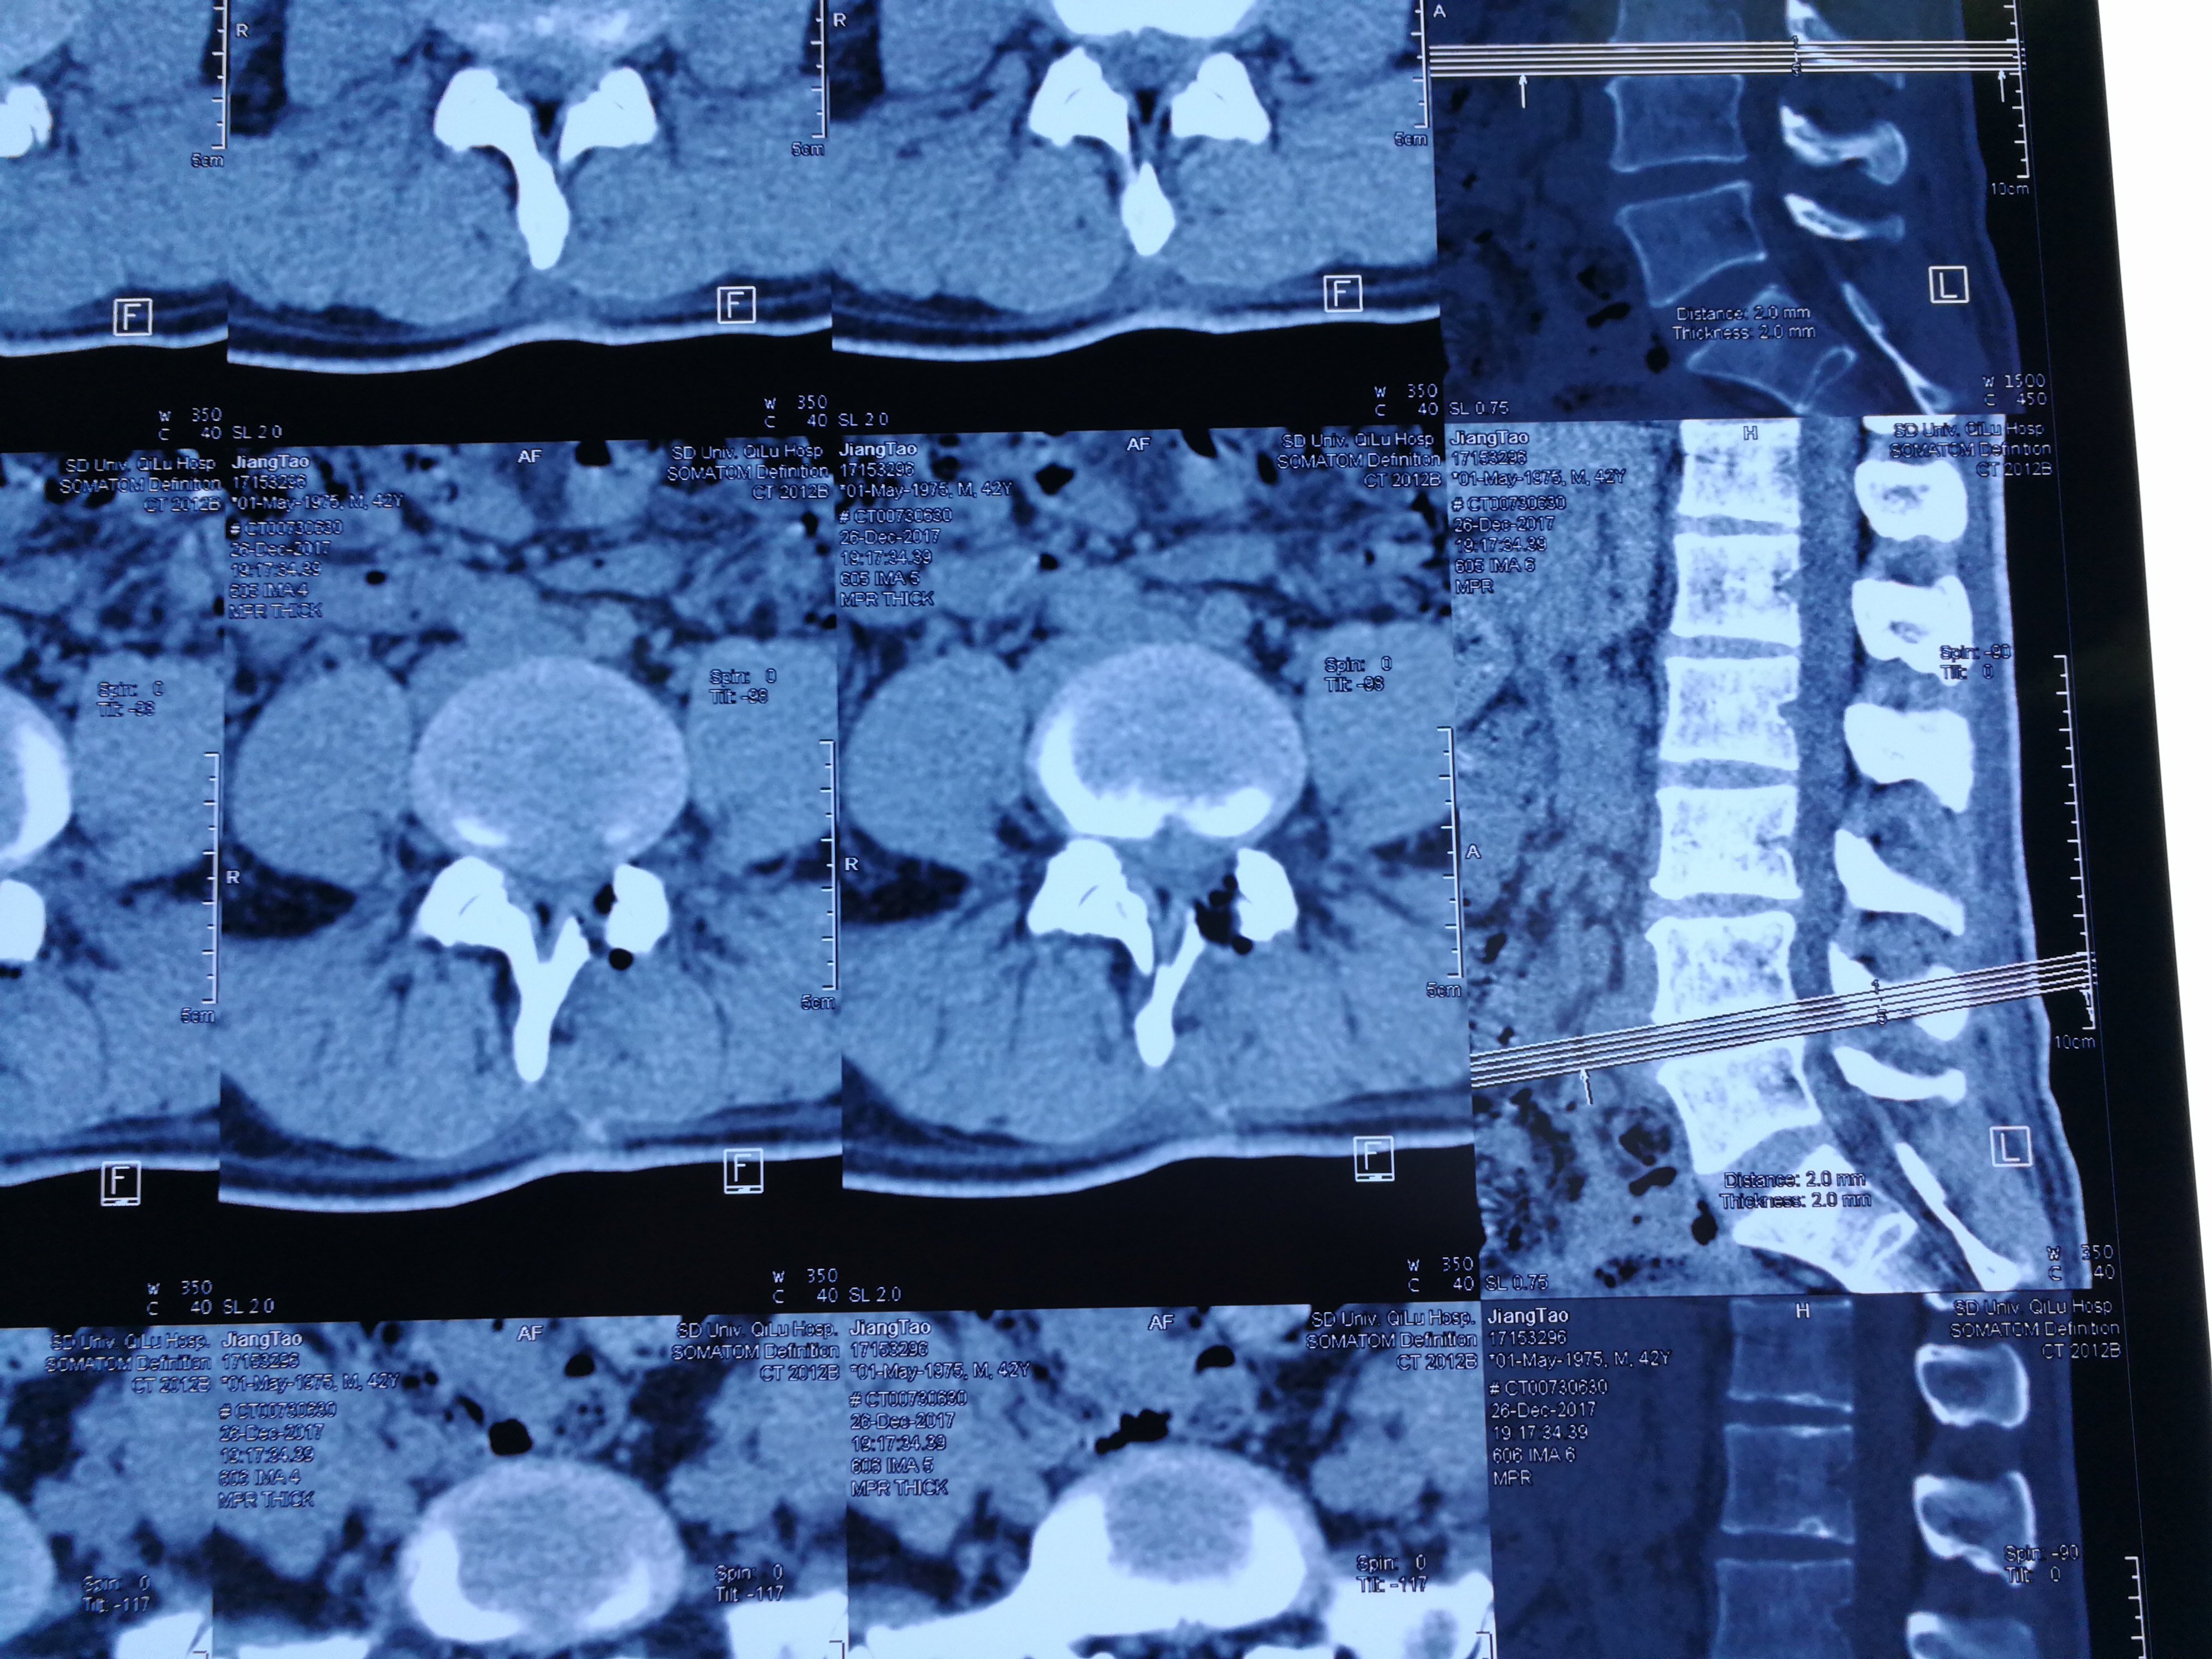

腰椎间盘突出症是困扰很多患者的疾病,主要发生在中年人身上。 很多中年患者朋友除了工作繁忙之外,还担心腰椎间盘突出症的存在,给工作和生活带来很大的压力。 下面介绍一些预防腰椎间盘突出症的运动。 我希望能有所帮助。